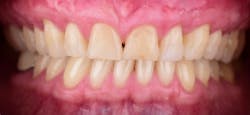

This new biological approach involving blood derivatives A-PRF and I-PRF combined with precision minimally invasive surgery for root coverage demonstrates faster healing without the need of a donor site. The morbidity of GDT is decreased and patient case acceptance is higher compared with traditional grafts. Before-and-after pictures are shown below (figures 15–22).